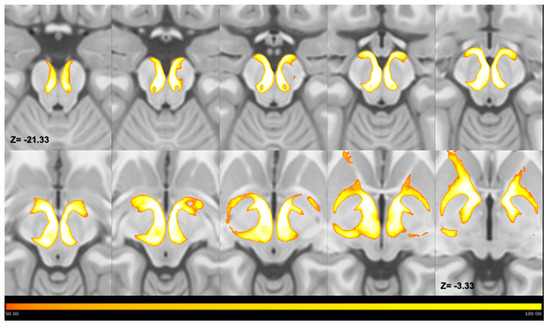

- Maps at the subject-level registered on the ICBM template were binarized and summed in order to obtain average maps representative of the whole sample. Furthermore, in this case, a threshold of 50% was applied to MPMs in order to retain only voxels overlapping by at least 50%.